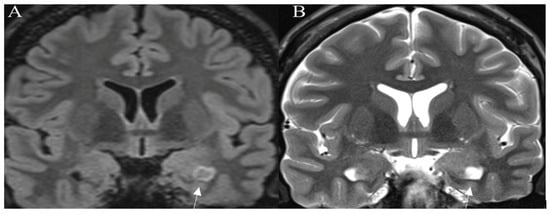

Standard Imaging Sequences